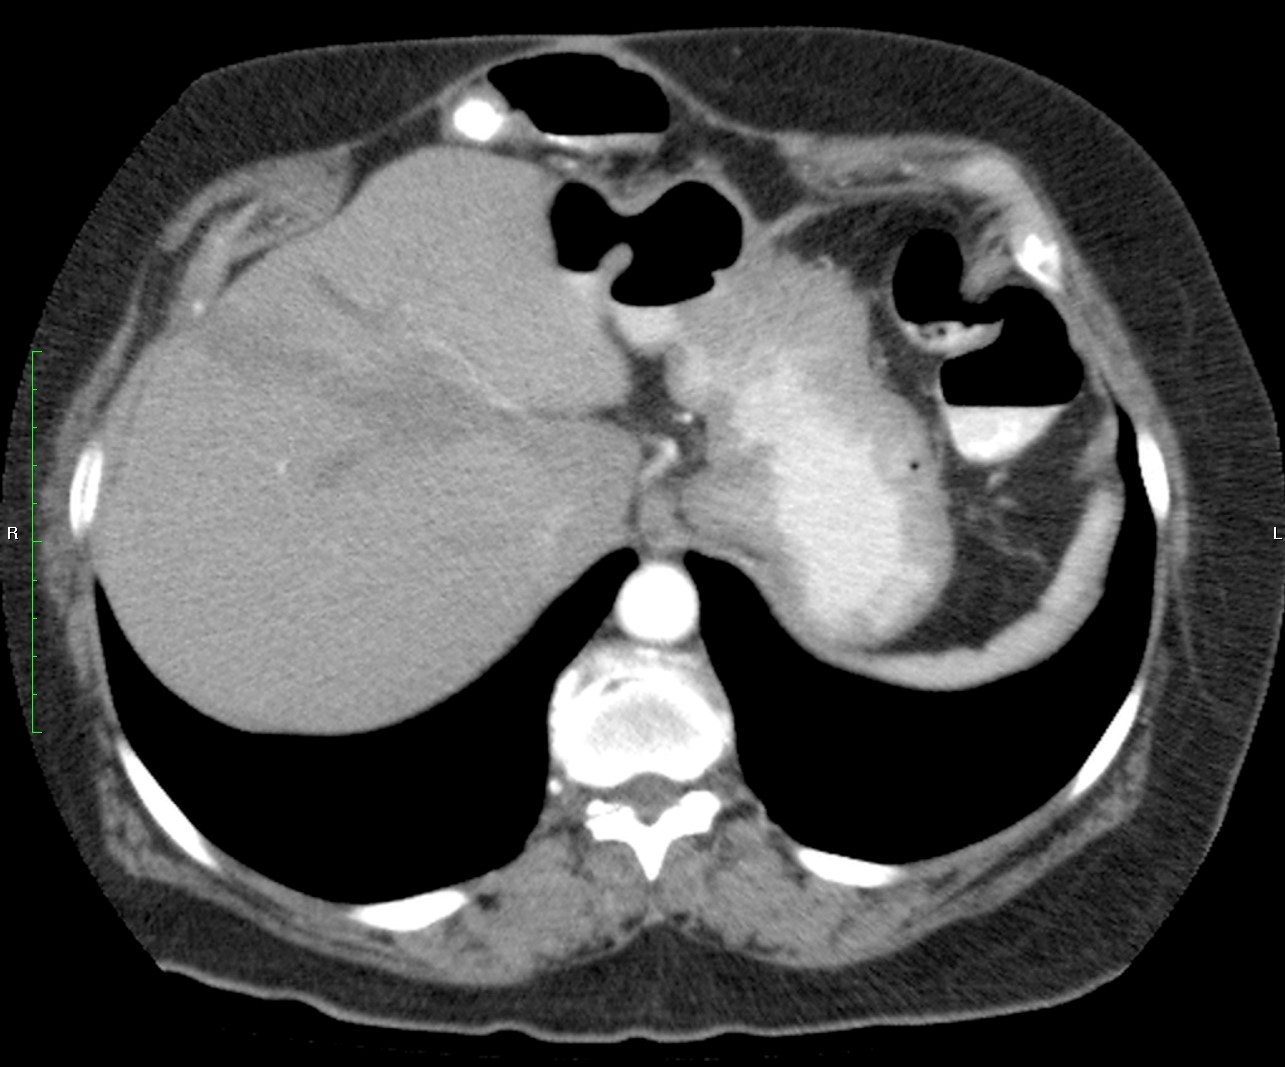

Mujer de 57 años.

Cuadro clínico de 1 mes de evolución caracterizado por distensión abdominal e hiporexia.